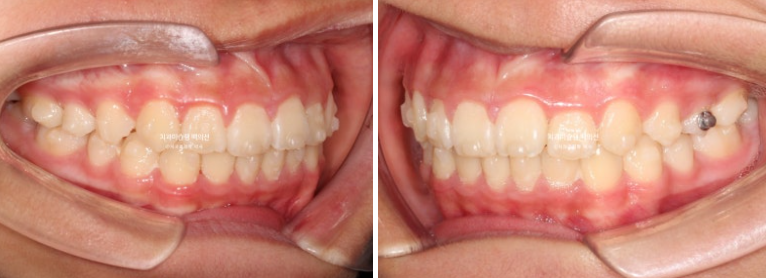

24.02

공간부족으로 인한 덧니가 심해 반대교합이 있습니다.

악궁확장을 통한 덧니배열을 목표로 인비절라인퍼스트 교정치료 권유드렸습니다.